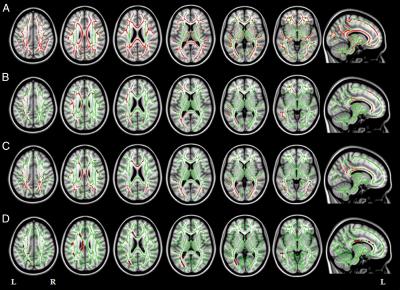

Study leader Massimo Filippi, M.D., and his team of researchers used diffusion tensor imaging (DTI) to assess the white matter tracts in 53 patients with three types of AD: early-onset AD and two atypical types of AD called focal syndromes because they affect localized parts of the brain.

DTI, a specialized magnetic resonance imaging technique that uses the movement of water molecules to characterize the microstructure of biological tissues, is highly sensitive to white matter degeneration.

"Our goal was to use DTI to identify similarities and differences in white tract damage across the AD spectrum and in relation to patterns of cortical atrophy," Dr. Agosta said.

The researchers' analysis of the images revealed that all of the patients had extensive white matter damage, and showed regional gray matter damage.

"The white matter damage in patients with focal AD syndromes was much more severe and widespread than expected and cannot be explained solely by gray matter atrophy which was more localized," Dr. Agosta said.

"In early-onset AD and atypical AD forms, white matter degeneration may be an early marker that precedes gray matter atrophy," Dr. Agosta said. "DTI has the potential to assess the extensive disorganization of brain networks in focal AD even before overt cognitive deficits become apparent."